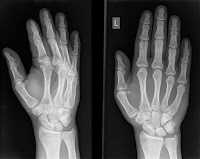

ROTURA DE HUESOS

Una fractura es una ruptura, generalmente en un hueso. Si el hueso roto rompe la piel, se denomina fractura abierta o compuesta.

Las fracturas en general ocurren debido a accidentes automovilísticos, caídas o lesiones deportivas. Otras causas son la pérdida de masa ósea y la osteoporosis, que causa debilitamiento de los huesos. El exceso de uso puede provocar fracturas por estrés, que son fisuras muy pequeñas en los huesos.